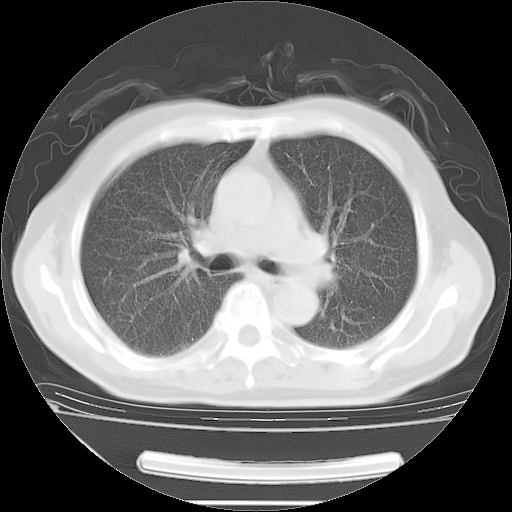

今天复查肺部CT,发现双肺广泛磨玻璃样改变。所以我把3月19日和5月9日相隔50天的肺部CT上传。请大家会诊。

2009年3月19日肺部CT片。

5月9日肺部CT(在4月27日齐鲁医院肺部CT描述部分肺组织磨玻璃样改变,12天后肺组织广泛磨玻璃样改变)

大致读了系列胸部CT:纵隔窗无明显异常,肺窗:从4、27至今:主要是双肺中下野外带可见毛玻璃样改变,目前处于急性肺泡炎阶段,至于原因考虑1、结替组织或胶原血管性疾病所致?2、恶性疾病如恶组在肺部所致的表现或细支气管肺泡癌?3、药物或其它原因如肺蛋白沉着症所致肺泡炎目前不太可能?总之,明天就去请我院的呼吸科、感染科、血液科和临免专家会诊哈。